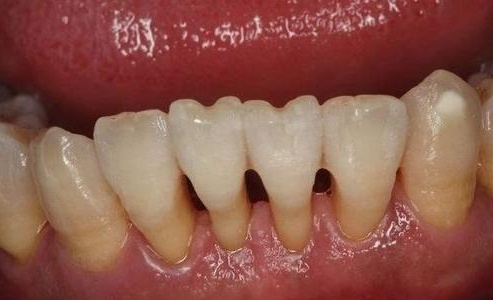

牙龈萎缩,常可导致“黑三角”出现。这是牙龈缺营养造成的吗?如果补充营养,又能否挽救呢?

牙龈萎缩是常见的牙病症状,为牙周炎患者的主要临床表现之一。由于牙周炎患者通常年龄较大,因此人们通常会将牙龈萎缩与营养缺乏联系起来。于是,就有了添加氨基酸的牙膏,据称可以除掉“黑三角”。然而,牙龈萎缩真的是营养不良造成的吗?补充营养结果又会是什么呢?

牙龈萎缩,专业上应该称之为“牙龈退缩”,它并非生理意义上的增龄性变化。因此,牙龈萎缩未必会发生在年龄较大的个体身上。换句话说,牙周健康的高龄者并不会出现牙龈萎缩。

牙龈萎缩的发生主要还是与长期的不良刺激有关。一类是机械刺激,比如不正确的刷牙、使用硬毛牙刷、牙膏的研磨剂过硬,又比如不良修复体、正畸力和咬合力;另一类是生物刺激,比如牙菌斑。牙龈在长期慢性炎症的影响下,最终会转为萎缩。

至于营养,至少目前还没有证据可以表明与牙龈萎缩有关。